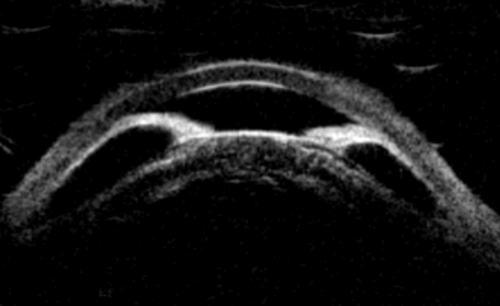

The treatment of pupil block is usually laser iridotomy, which enables equalisation of pressures between the anterior and posterior chambers. Following treatment, the iris returns to a straighter configuration and the trabecular meshwork may be opened unless other mechanisms such as plateau iris are present. Repeating the UBM post iridotomy allows quantitative evaluation of the angle and iris profile, and identifies any other underlying mechanisms (Figure 1b). The identification of PAC(G) morphology is especially important if and when laser iridotomy is not successful.

Before PI pupil block causing angle closure.

After PI pupil block resolved; angle open.

Figure 1b (top and above): Pupil block before and after peripheral iridotomy.